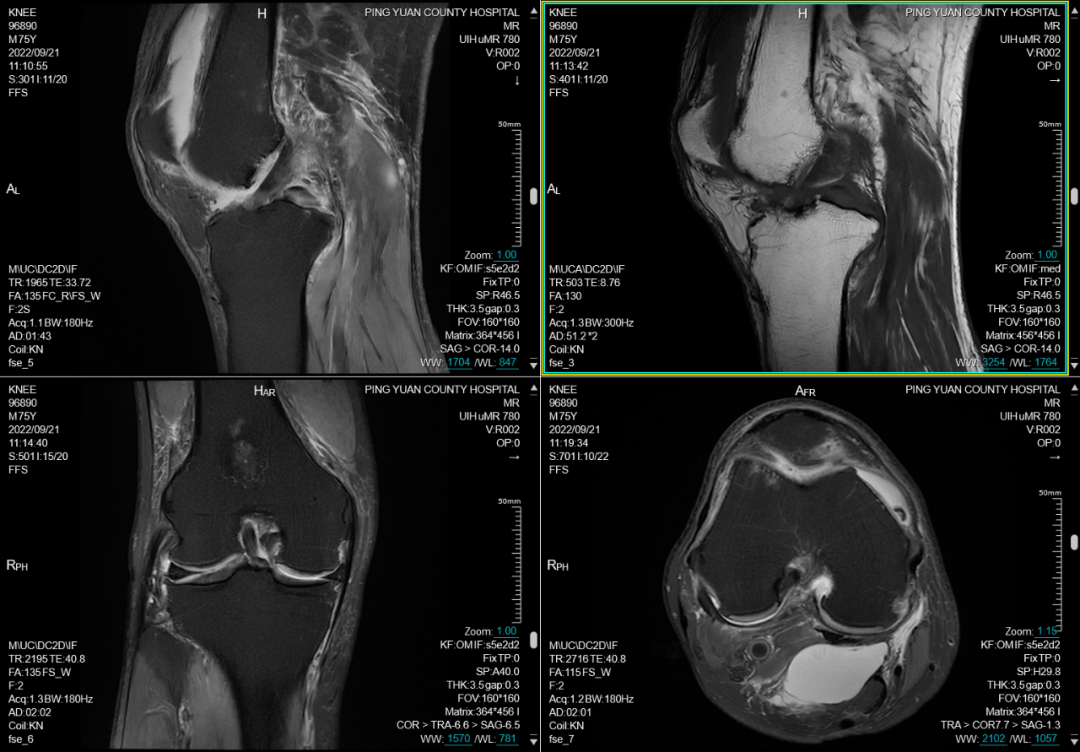

六、在四肢及关节检查方面:图像更清晰,后处理功能更丰富

MRI彻底变革了骨骼肌肉结构的成像,主要应用于创伤、关节炎、肿瘤和感染等方面。在创伤方面可显示平片或CT不能显示的病变如骨挫伤或骨小梁骨折,隐匿性骨折平片甚至CT易漏诊,而MRI能清晰显示。MRI是无创评估关节内软骨的最佳检查手段,能清晰观察软骨细微变化。

(膝关节MR检查及后处理)